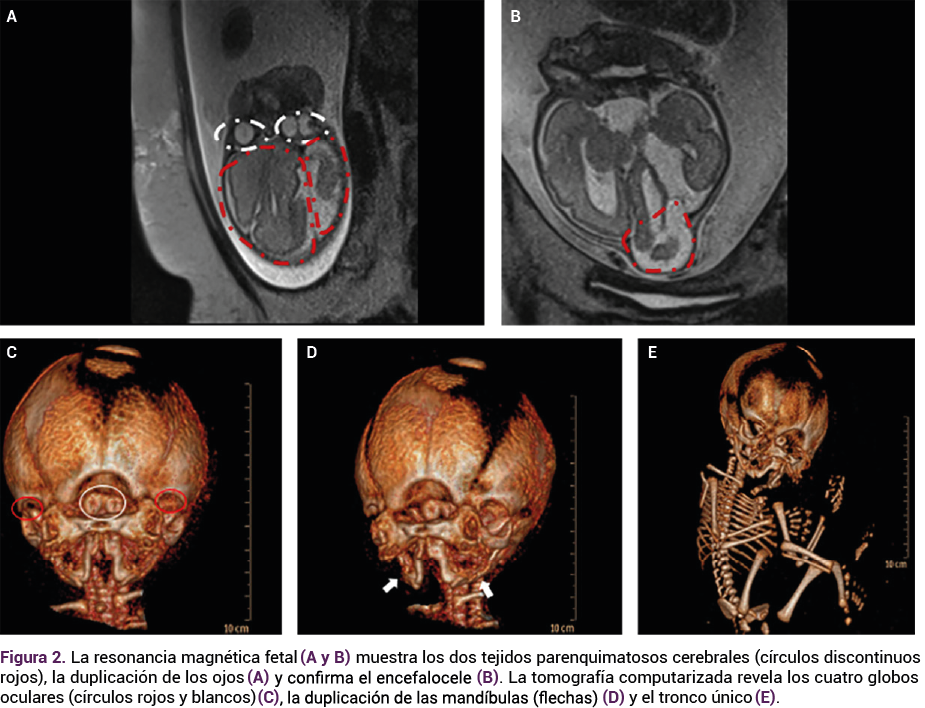

La evaluación detallada de la anatomía fetal a las 27 semanas mostró un cráneo único, con un encefalocele parietal, macrocefalia, interrupción de la línea media con fusión de los ventrículos laterales, sospecha de agenesia del cuerpo calloso, hipoplasia cerebelosa y cisterna magna agrandada. La cara tenía cuatro ojos, dos orejas, dos narices, dos bocas y dos mentones con micrognatia; estos rasgos se confirmaron y caracterizaron con ecografía tridimensional. No se identificaron otras anomalías y la ecocardiografía fetal se reportó normal.

<strong>Figura 1</strong>

Figura 1. Hallazgos por ultrasonido 2D/3D con duplicación facial y encefalocele, con caracterización detallada de rasgos craneofaciales.

El tamiz prenatal, con ecografía bidimensional y tridimensional, puede detectar las malformaciones craneofaciales.15 En muchos casos, una exploración dirigida requiere de otras técnicas adicionales que permitan mejorar la precisión del diagnóstico por ultrasonido.15 En el caso aquí comunicado, el diagnóstico prenatal de duplicación facial completa y encefalocele se estableció con base en una ecografía bidimensional y la ecografía 3D facilitó un examen detallado de los rasgos faciales, lo que finalmente confirmó el diagnóstico de diprosopus.15 Las imágenes de la ecografía 3D también desempeñaron un papel decisivo en la ayuda a la paciente y su familia para comprender la naturaleza compleja de esta malformación.15 Garel y su grupo reportaron la importancia de las técnicas adicionales: la resonancia magnética como método complementario en la evaluación de las afecciones craneofaciales, que destacan la mejor visualización de las estructuras, la ausencia de radiación ionizante y la calidad de las imágenes a pesar de la obesidad de la madre o la cantidad de líquido amniótico.15 Esos mismos autores reportan la importancia de la tomografía computada, teniendo en cuenta el principio ALARA en la aplicación de bajas dosis de radiación.15 Para el estudio del caso aquí comunicado, la resonancia magnética fetal aportó información valiosa del sistema nervioso central al demostrar la duplicación cerebral y la agenesia del cuerpo calloso.15 A pesar de haberse diagnosticado al finalizar el segundo trimestre, la combinación de la ecografía detallada y la resonancia magnética proporcionó información prenatal precisa.15 Esto guió la elección de la paciente con respecto al control del embarazo y permitió a la familia y a los médicos implementar un plan de parto integral.15